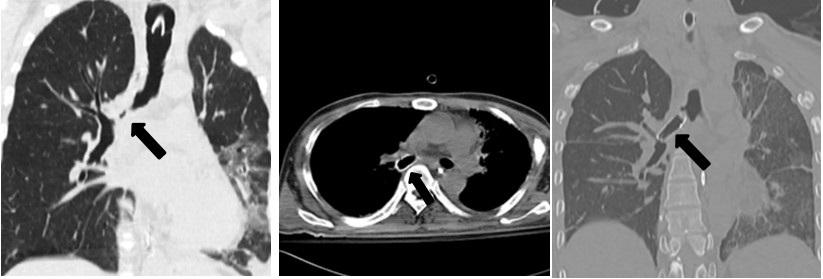

气管支架治疗5例:CT或气管镜明确诊断为软骨环破裂和(或)软化致气管塌陷后,经气管镜置入金属或硅酮支架。1例左主支气管塌陷,置入金属支架1枚,18 d后取出,但管壁仍软化塌陷、脱机困难,予置入Y形硅酮支架,1年后拔出(图 1 A~C),恢复良好。1例隆突上方气管及左主支气管广泛软骨环形破裂、憩室形成,右主支气管开口处软化、塌陷狭窄,置入金属支架1枚,3周后取出(图 2 A~C),恢复良好。1例因左侧气胸、左主支气管塌陷,置入金属支架1枚,术后出现左肺不张,多次经气管镜吸痰治疗,术后2周取出,左肺复张(图 3 A~C)。另2例气管塌陷患者,各置入金属支架1枚,2~3周后取出。5例患者置入支架后均观察到粘痰堵塞,每日予气管镜吸出。5例患者均效果良好,未见支架移位,支架取出后随访6个月以上,未出现气道狭窄。

| A 为左主支气管狭窄、气胸;B 为金属支架植入术后3 d左肺不张;C 为支架取出后气管通畅、左肺复张 图 3 左主支气管损伤置入金属支架1例 |